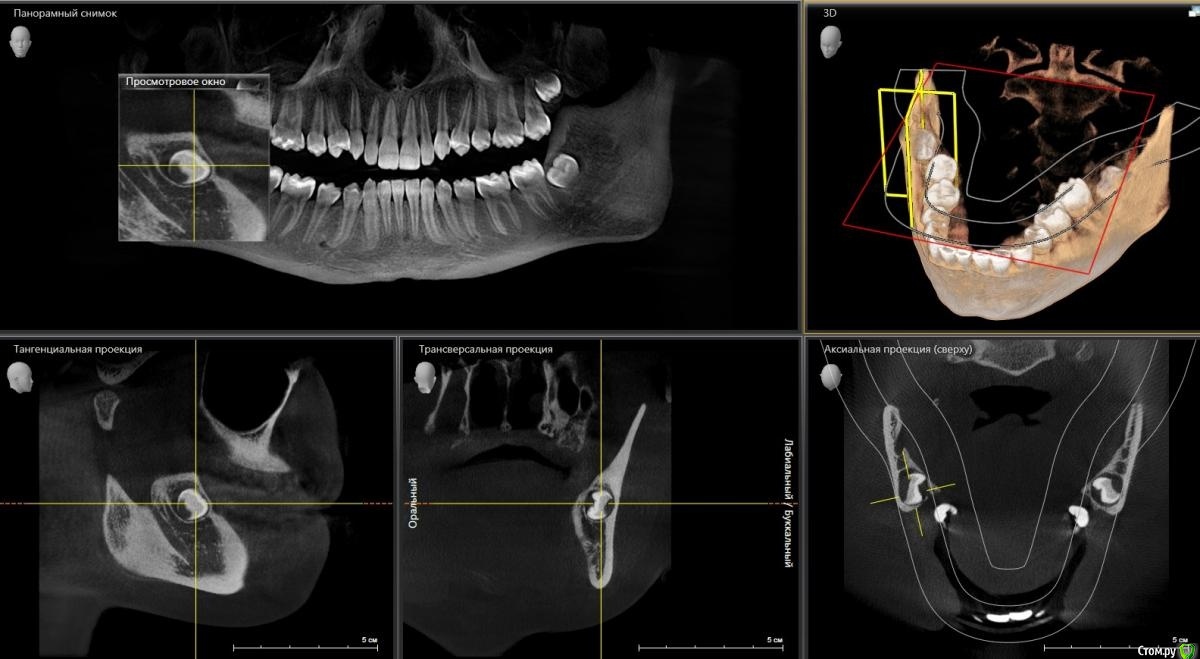

___49___ Опубликовано 12 ноября, 2020 Поделиться Опубликовано 12 ноября, 2020 (изменено) Немного выше в теме скидывал возможные анатомические вариации нижней челюсти , при которых во время удаления 8ки проталкивают апекс язычно .Встречается не часто (реже перфорации верхнечелюстной пазухи ) , но ситуация на мой взгляд менее приятная нежели перфа. Ниже фото пациента , которого я увидел спустя 5 дней после подобного неудачного удаления. Тризм на 1 палец, пациент принимает уже второй курс антибиотиков, t -37-38 , глотание болезненно , флюктуирующего инфильтрата не определяется , кожа в складку собирается, гнойного отделяемого из лунки нет. С молитвами , под торусальной + инфильтрационной анестезией , доступом через внутри ротовой разрез , через минут 10 не активного ( так как тризм , крупный язык ) поиска , удалось поймать "беглеца" , экссудат серозного характера, из лунки удален 2ой апекс, кюретаж, промыта р-ром метронидазола , в лунку введен альванес гель, от дренажа отказался ( при попытке установить , после функциональной пробы - попросил несколько раз открыть и закрыть рот , сглотнуть слюну, дренаж попытался скрыться в глубине мягких тканей) , рану также промыл р-ром метронидазола. Пациент продолжил прием ранее назначенных ему антибиотиков. Осмотры на 2 ой и 4 ый день , динамика положительная. По прошествии 2 недель , открывание рта в полном объеме , t в норме....апексы пациент забрал на память ) . Изменено 12 ноября, 2020 пользователем ___49___ 11 Ссылка на комментарий